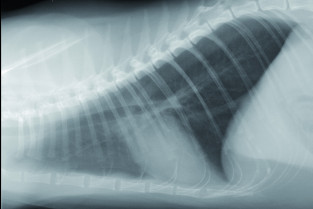

- décrire les principes à respecter pour obtenir une radiographie thoracique de bonne qualité ;

- adopter une méthodologie pour interpréter des radiographies thoraciques chez les carnivores domestiques.

TD de radiographie thoracique